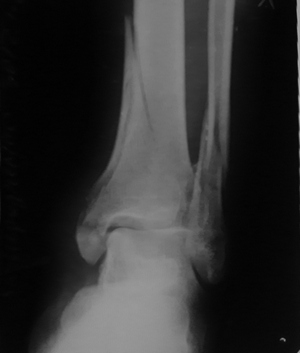

Добрый день, высылаю фото после операции

Кликните для загрузки файла DSC01505.JPG

58KB (59990 bytes)

Снимок мелковат, можно только сказать, что грубых смещений не видно. То есть картина оптимистичная.